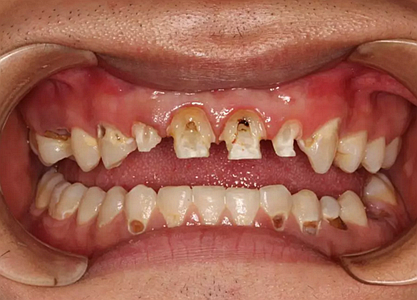

現(xiàn)在剩下的任務就是為我其他的兄弟姐妹們治療了。需要做根管的做根管,需要做冠的做冠,需要樹脂充填的做樹脂充填。前前后后主人帶我們進行了12次的復診,歷時6個月,現(xiàn)在的我們是這樣的

再來看看曾經的我們